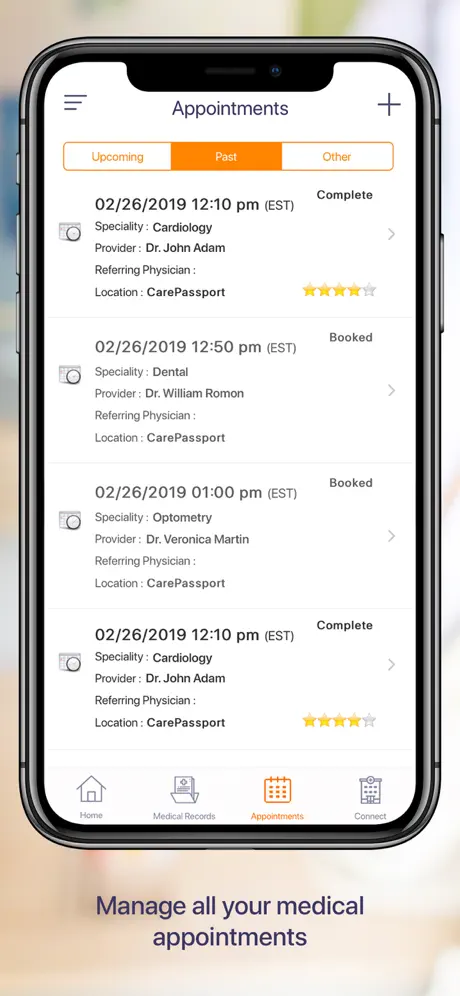

CarePassport es una plataforma universal de próxima generación que ofrece a los pacientes un punto de acceso único para recolectar, almacenar, compartir y administrar sus citas y registros médicos.

La aplicación permite a los pacientes acceder de forma segura a sus datos médicos o proxies familiares, programar citas, ver imágenes médicas, informes clínicos y de laboratorio de diferentes proveedores con la capacidad de descargar, archivar y compartir utilizando la tecnología de computación móvil más avanzada.

- Obtenga una cita médica con un solo toque

- Obtenga una cita médica con un solo toque